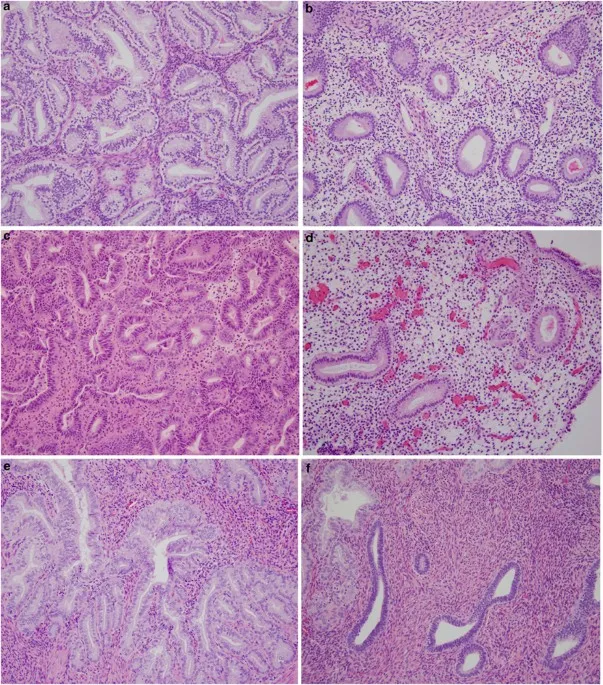

- WHO 2014 Classification & Progression Risk:

Category Key Feature Progression to Carcinoma Hyperplasia without Atypia Glandular crowding, no atypia Low risk (~1-3%) Atypical Hyperplasia / EIN Cytological atypia present High risk (~25-45%) - Molecular: PTEN tumor suppressor gene inactivation is a common early event in EIN.

⭐ Atypical hyperplasia/EIN is considered a direct precursor to endometrioid endometrial adenocarcinoma.

- FIGO Grading (Endometrioid): Based on % solid growth.

- Grade 1: ≤5% solid growth

- Grade 2: 6-50% solid growth

- Grade 3: >50% solid growth